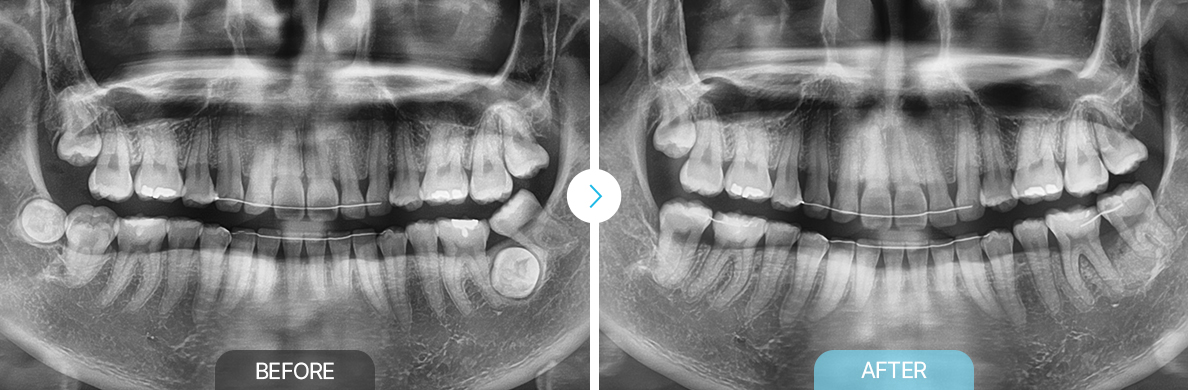

맹출유도교정

부천상동 맹출유도교정, 부천치과, 맹출유도교정 상동 맹출유도교정 부천연세퍼스트치과, 교정치과 부천상동, 맹출유도교정 부천교정치과